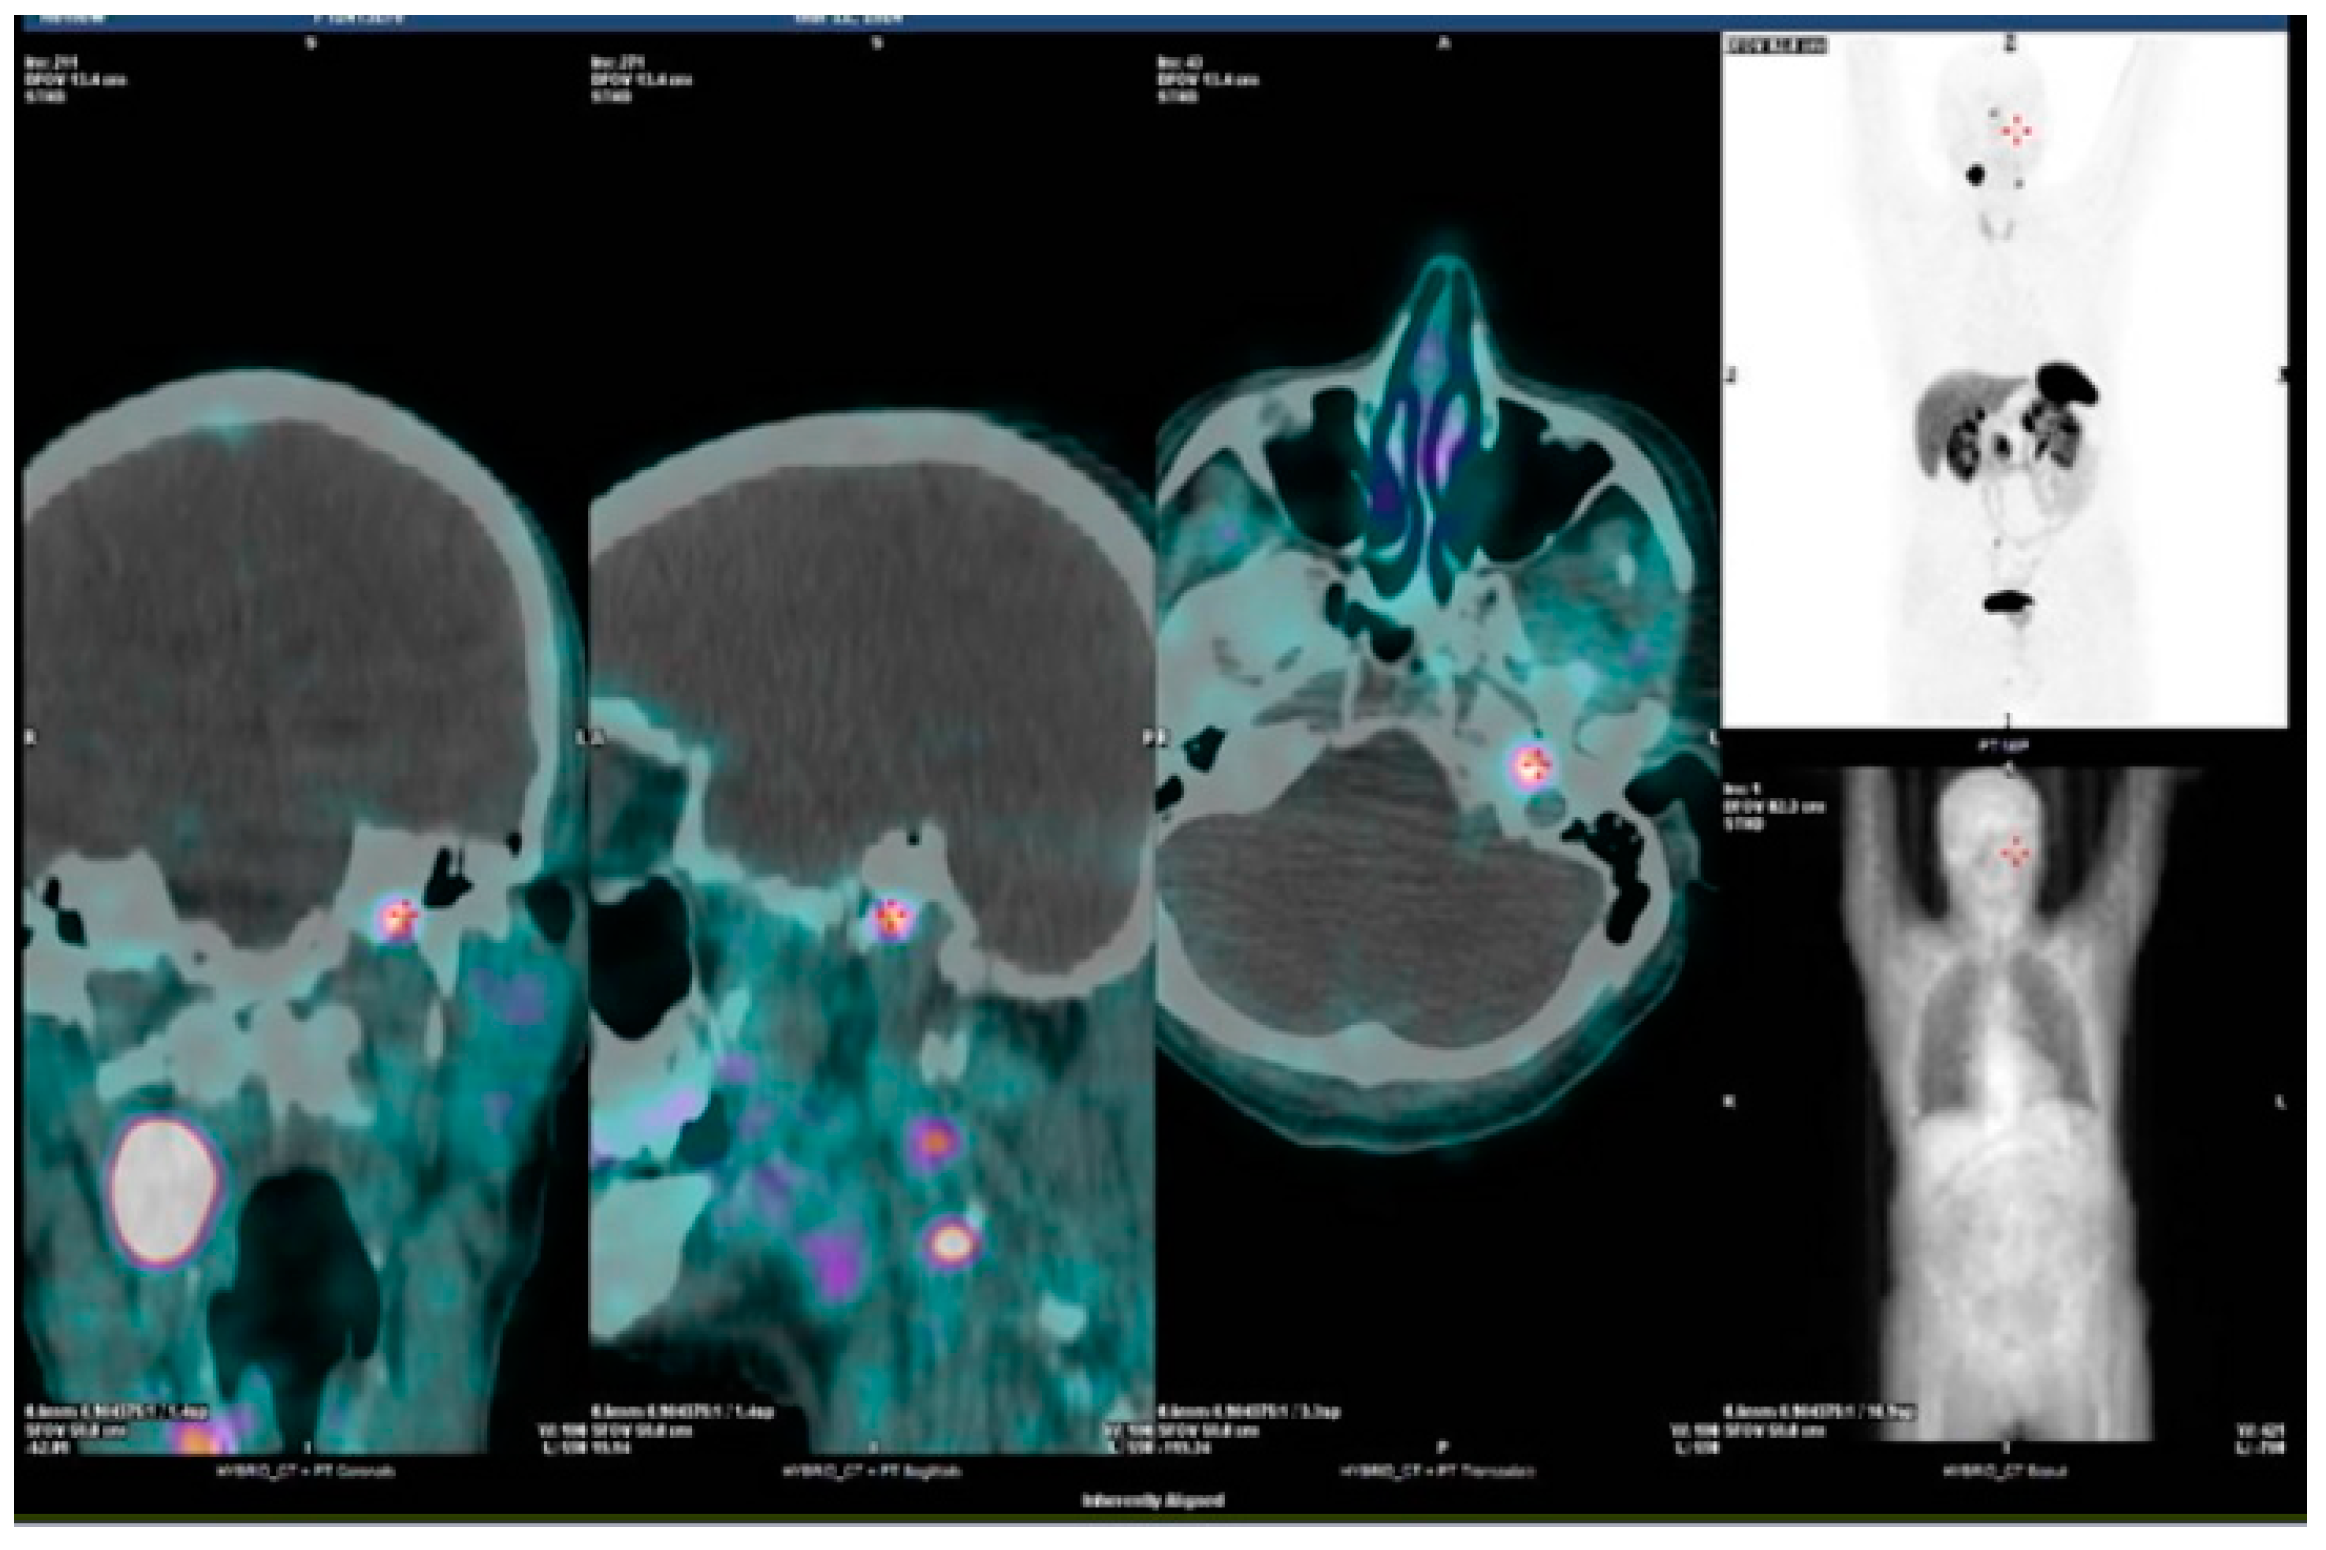

- Extra-adrenal localization is more typical for cluster-1 PGLs, while adrenal tumors belong mostly to cluster-2, so in the choice of functional imaging, there is no doubt in preferring [68Ga]-DOTA-SSA PET/CT for extra-adrenal tumors and [18F] FDOPA PET/CT for adrenal tumors.